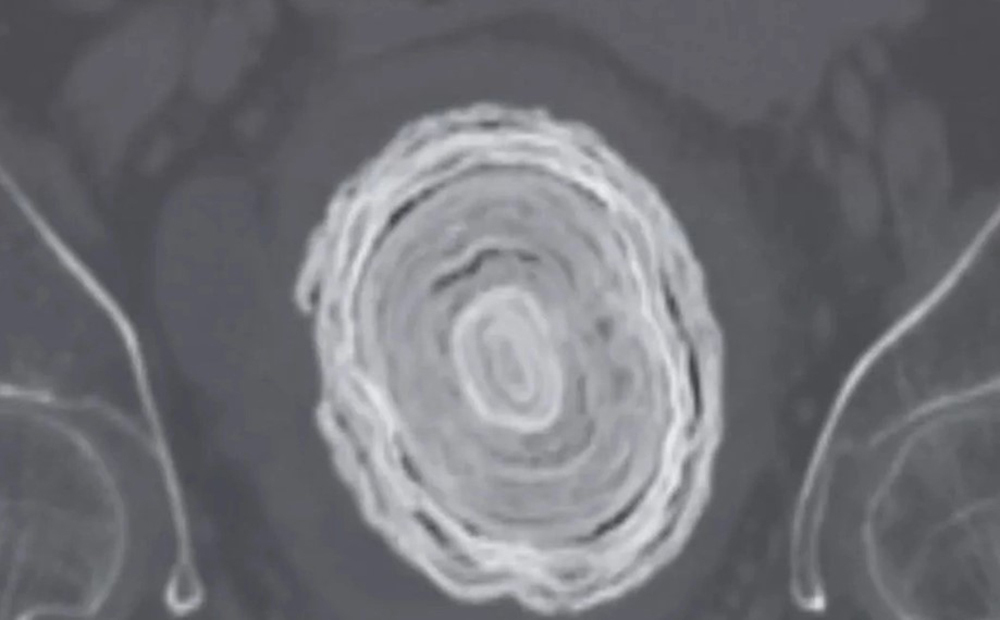

Viên sỏi bàng quang to như quả bóng chày trong cơ thể người phụ nữ. Ảnh: The Mirror

"Một số viên sỏi bàng quang tạo thành các lớp do sự thay đổi theo từng đợt trong quá trình lắng đọng khoáng chất và thành phần nước tiểu theo thời gian", các bác sĩ viết. Để giúp người phụ nữ này, trước tiên các bác sĩ đã điều trị bằng thuốc kháng sinh và sau đó sử dụng tia laser để phá vỡ viên sỏi lớn.